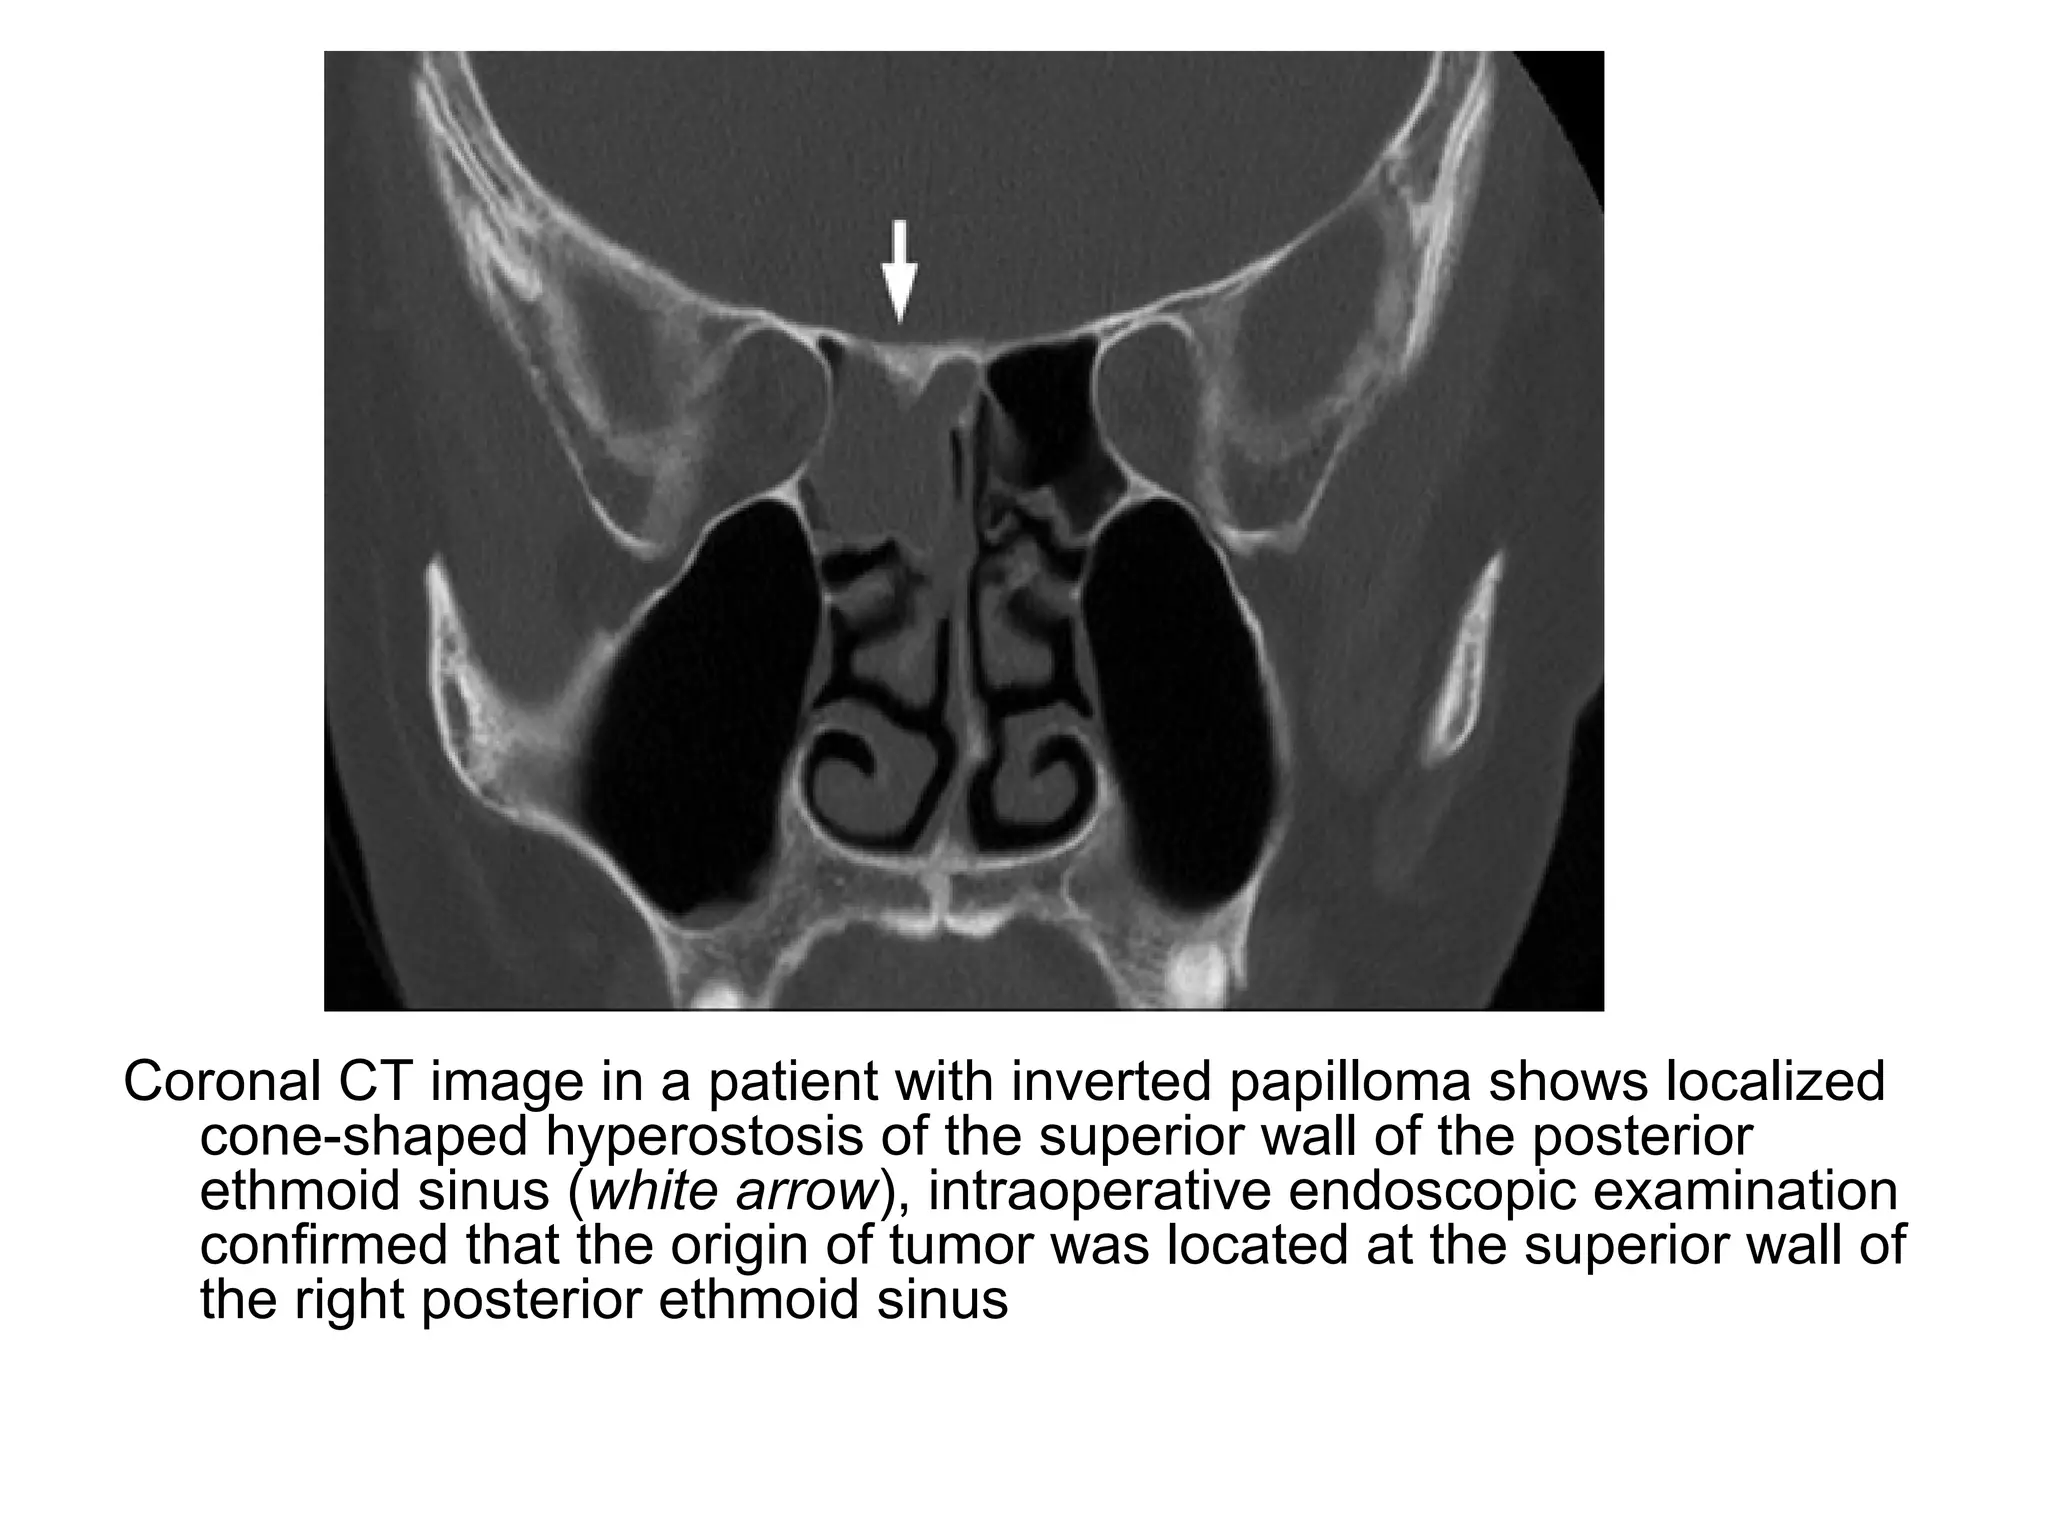

Coronal CT image in a patient with inverted papilloma shows localized

cone-shaped hyperostosis of the superior wall of the posterior

ethmoid sinus (white arrow), intraoperative endoscopic examination

confirmed that the origin of tumor was located at the superior wall of

the right posterior ethmoid sinus